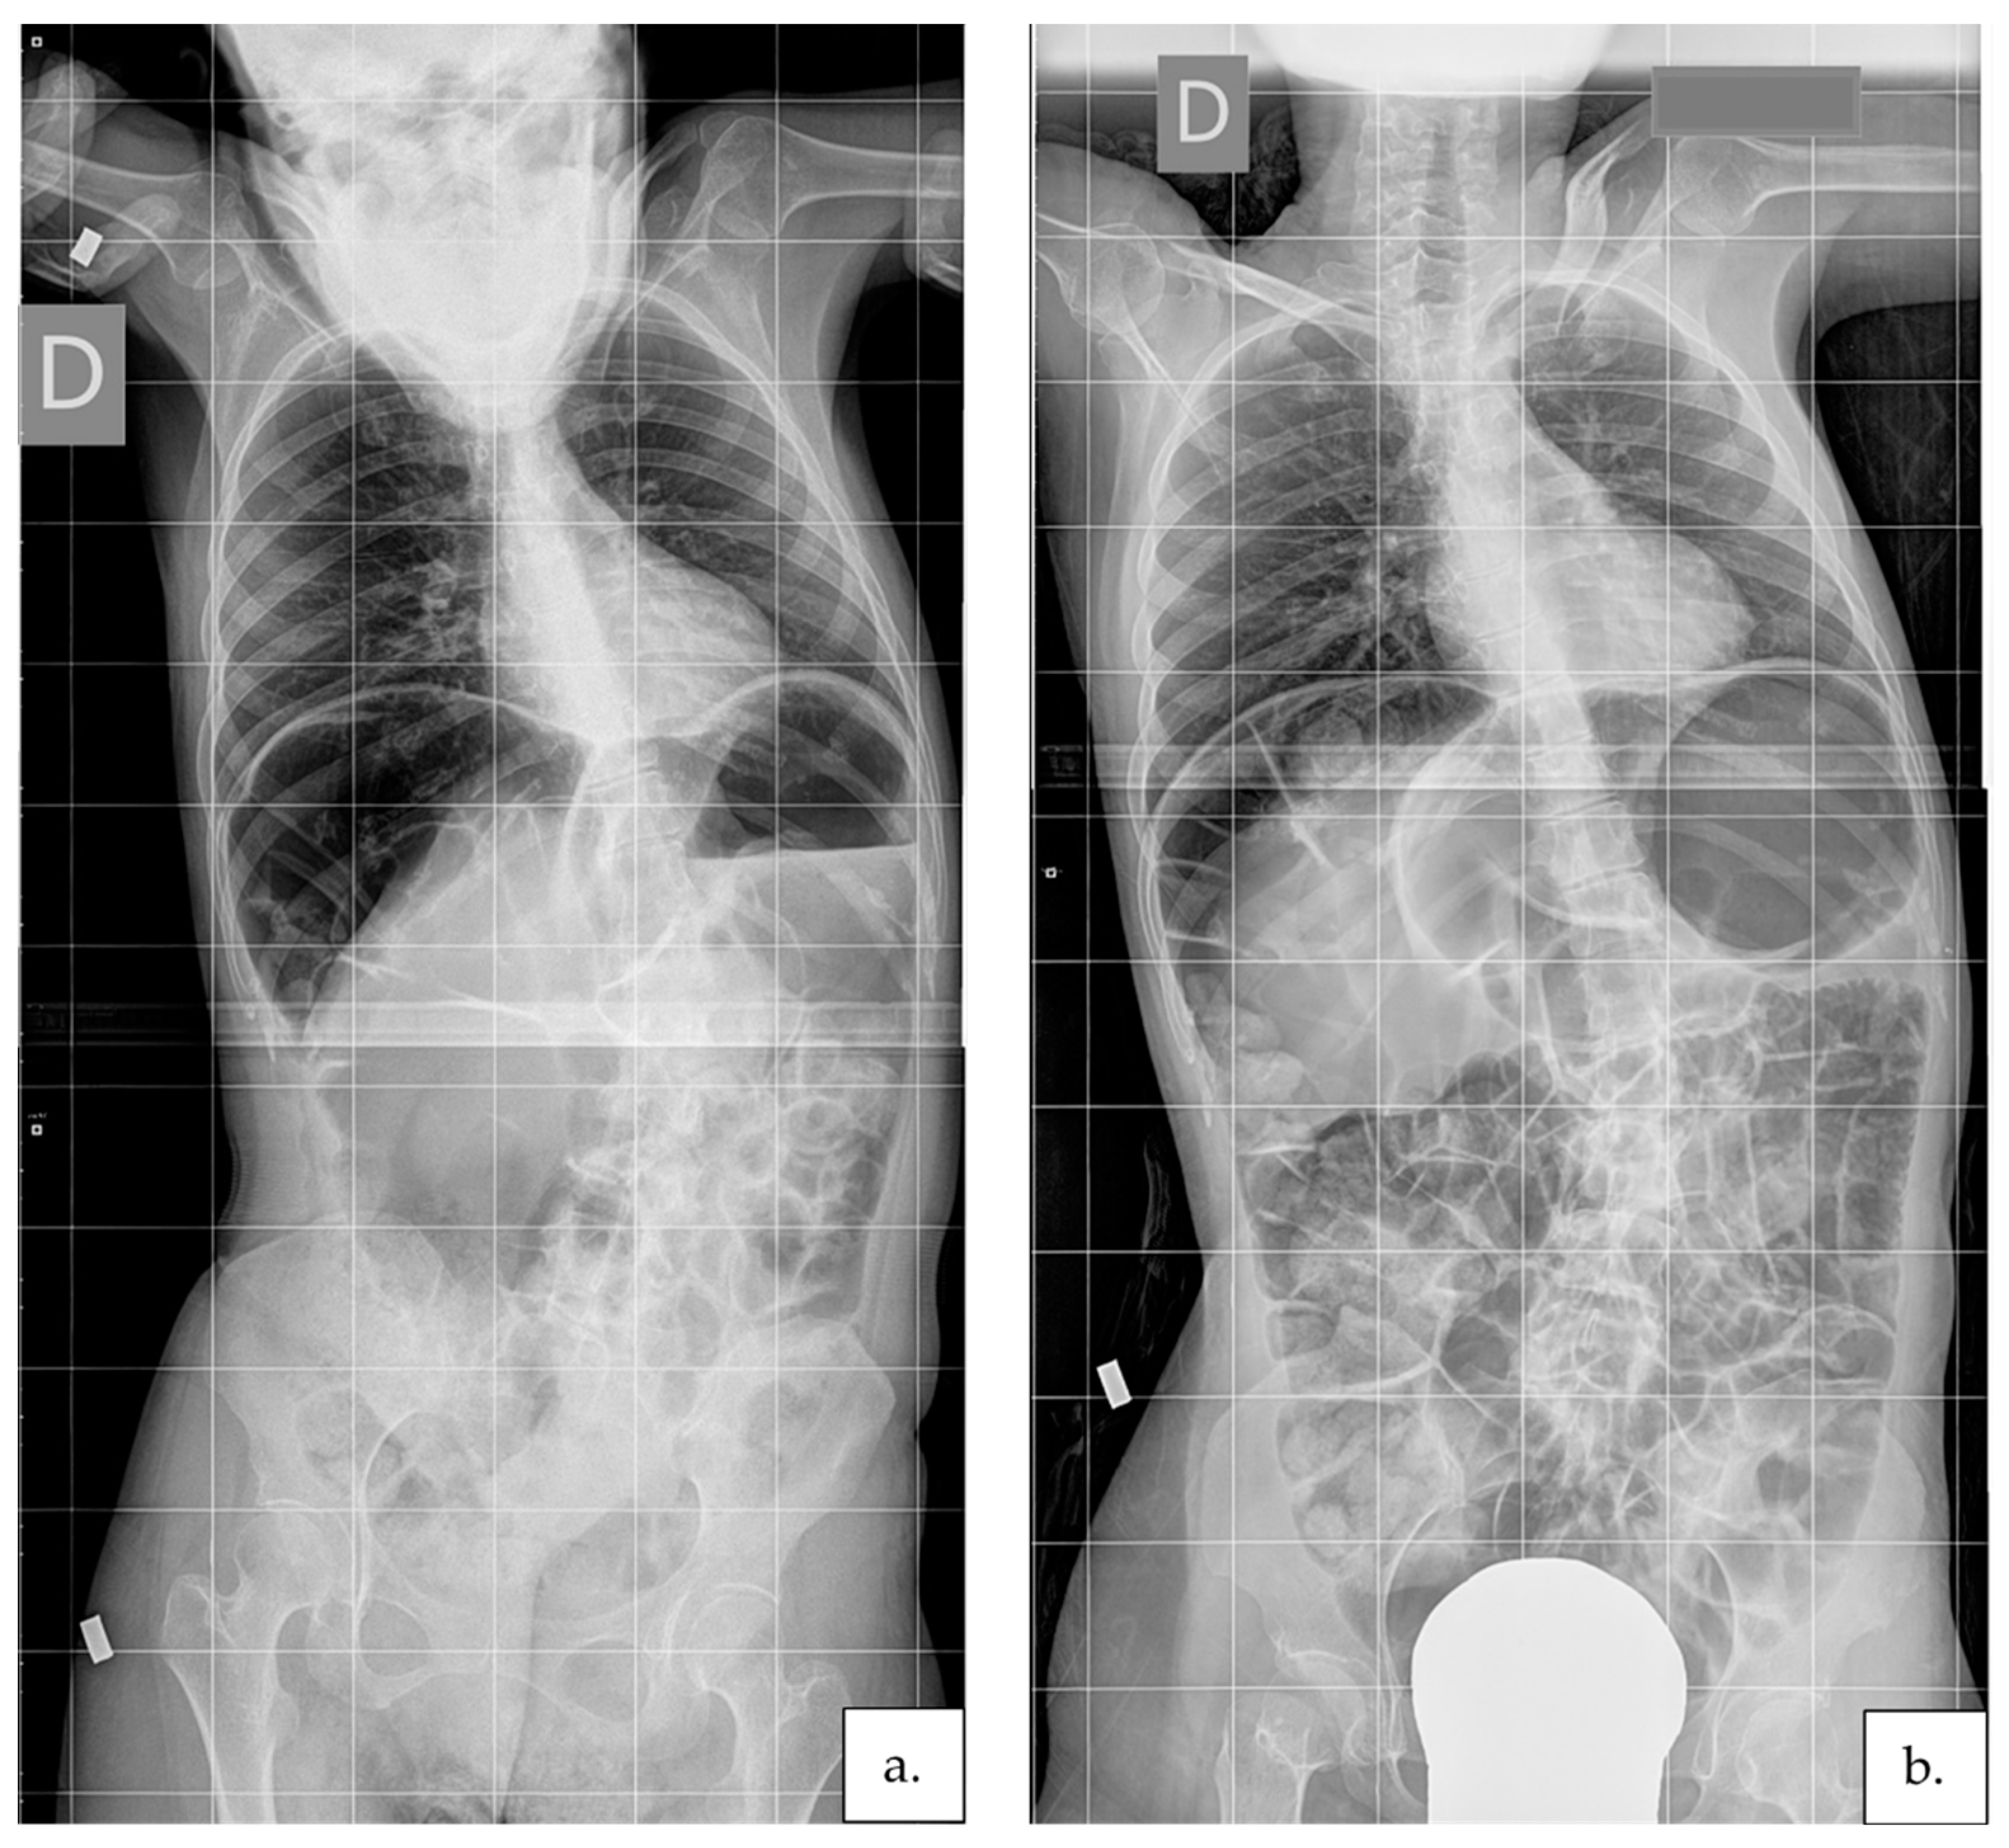

2.3.4. Scoliosis Severity